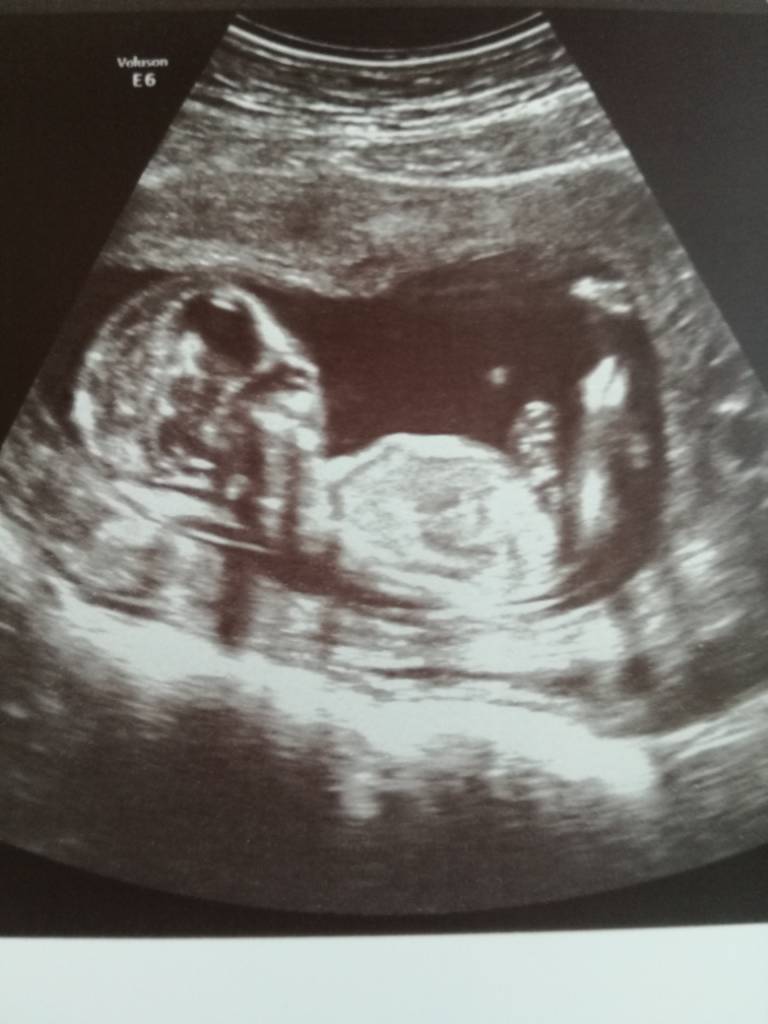

Cudnie ![emoji7]Nadrobie was wieczorem chce napisac ze jestem po usg i wszystko jest w porzadku, male skakalo ruszalo raczkami i nozkami , cudowny widokprzyziernosc 1.7mm maluszek ma 6,3 cm termin sie przesnal z usg i jest na 14.12 takze dzidzi rosnie jak na drozdzach

serduszko 170 uderzen no i na 90% chlopiec

moj wymarzony hehe jestem przeszczesliwa.

Nadrobie was wieczorem chce napisac ze jestem po usg i wszystko jest w porzadku, male skakalo ruszalo raczkami i nozkami , cudowny widokprzyziernosc 1.7mm maluszek ma 6,3 cm termin sie przesnal z usg i jest na 14.12 takze dzidzi rosnie jak na drozdzach